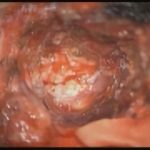

摘出 前

摘出 中